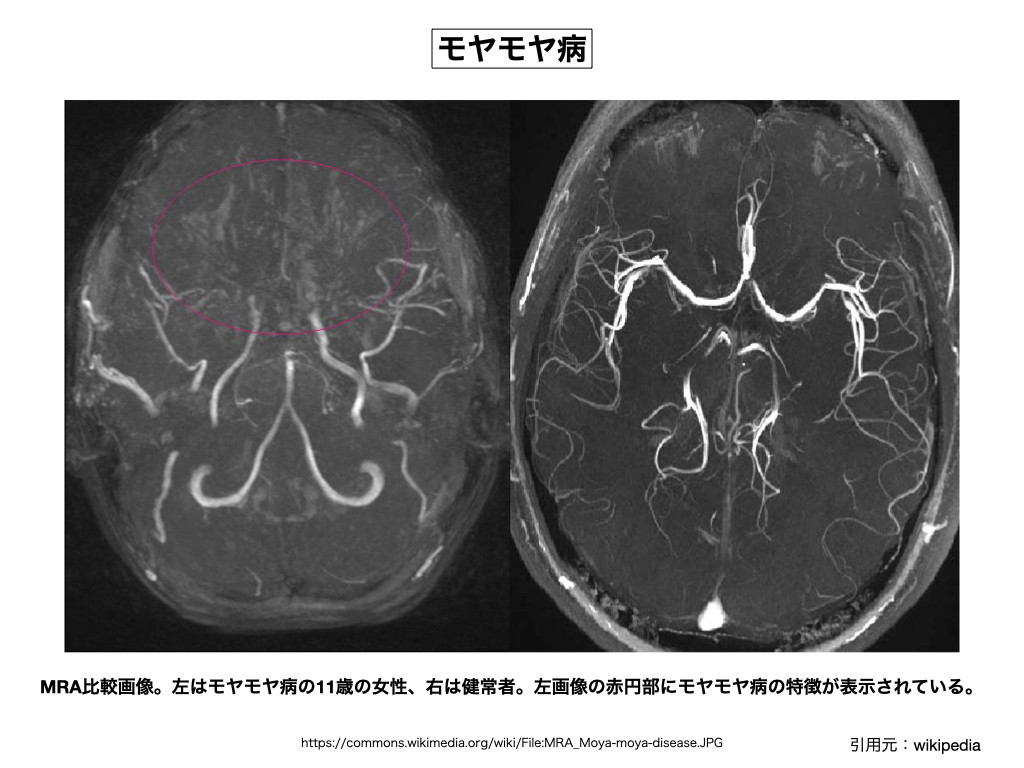

002) モヤモヤ病(ウィリス動脈輪閉塞症)

※ 脳底部に異常血管網が見られる脳血管障害の事で、特に大脳動脈輪の主幹動脈(中大脳動脈近位部: 内頸動脈終末部)の閉塞や狭窄によって代償的に形成された側副血行路の未熟な血管網(モヤモヤ血管)の事を指している。早い話が、ウイリス動脈輪の血管内部で閉塞や狭窄が発生するから、それを補う為に細くて未熟な代替え血管網が発達し、その血管網が様々な脳障害を発生させている。なぜ、特殊な脳領域に血管の詰まりが発生するのか、その原因は良く分かっていないが、家族単位で発生する事例も多く、その様な意味で遺伝病の一種とみなされている。実はこの病気も神々(魔界神)が引き起こす病気の一つで、ウィリス動脈輪の内頸動脈終末部に魔界武器の一種である「ヌイテ材」を詰めて動脈閉塞を発症させるのがその目的である。「ヌイテ材」とは脳血栓を引き起こすアストラルの詰め物であり、また「ウテ材」とは心臓の冠状動脈に仕込む詰め物であって、両者は典型的な魔界武器であり、基本的には肉体の命を狙う物である。魔界関係者がいる家族の身内に良く発生し、また魔界契約時にも武器を挿入されるケースも多い。挿入された魔界武器を外しても、症状の緩和は見られるが、一度形成されてしまった未熟な側副血行路は除去する事が出来ない。